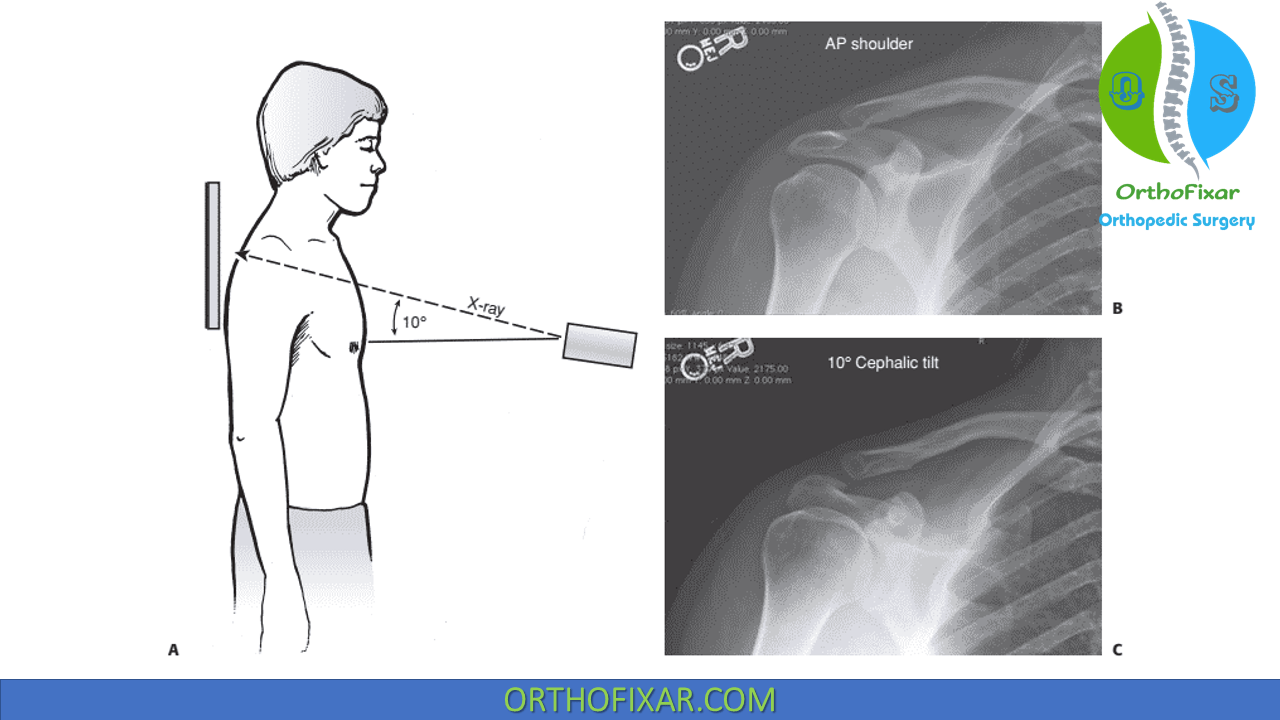

Zanca View Chest X Ray . The axillary view is important for detection of. Standard radiography of the acromioclavicular joint includes a frontal view of the shoulder, axillary view, and scapular y view. Sie dient insbesondere der beurteilung distaler. Reprinted from the journal of the. The view optimizes visualization of the. Ó1999 american academy of orthopaedic surgeons. Diagnosis is made with bilateral focused shoulder radiographs to assess for ac and cc interval widening. A zanca view should also be obtained as it provides the most accurate radiographic assessment of the ac joint. Treatment is immobilzation or surgical reconstruction depending on. Download scientific diagram | zanca view radiograph demonstrating the anatomy of the acromioclavicular joint. The zanca view is used in the assessment of acute and chronic acromioclavicular joint injuries.

The zanca view is used in the assessment of acute and chronic acromioclavicular joint injuries. Diagnosis is made with bilateral focused shoulder radiographs to assess for ac and cc interval widening. Download scientific diagram | zanca view radiograph demonstrating the anatomy of the acromioclavicular joint. Reprinted from the journal of the. Ó1999 american academy of orthopaedic surgeons. Sie dient insbesondere der beurteilung distaler. A zanca view should also be obtained as it provides the most accurate radiographic assessment of the ac joint. Standard radiography of the acromioclavicular joint includes a frontal view of the shoulder, axillary view, and scapular y view. The axillary view is important for detection of. The view optimizes visualization of the.